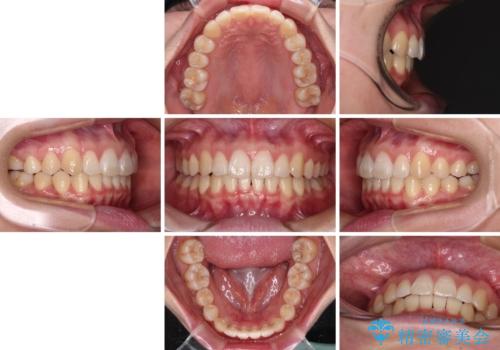

咬合高径の挙上により上顎前歯の突出感も改善することができ、整った口元となりました。

- 上顎前歯の隙間を気にして来院された患者様です。

下顎前歯が上顎前歯に食い込むような咬み合わせにより、上顎前歯が開いてしまっていたため、咬合高径の挙上により突き上げを改善するよう、インビザラインにより矯正治療を行うこととしました。